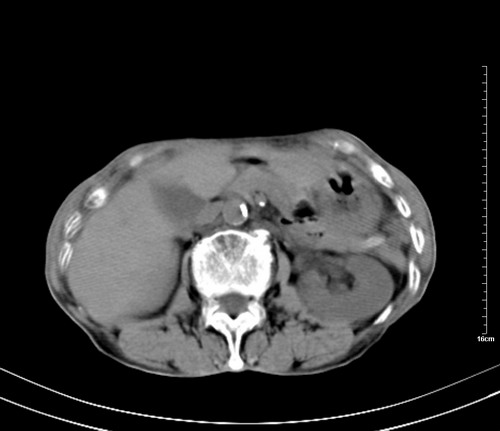

病人,女,79岁,主要因腹疼二月入院,彩超,肝,胆,脾,未见异常,胸透上消化道造影未见异常,化验白细胞增高,内科医生让做胸部ct检查,因为熟人多做了腹部(外科会诊考虑胆囊炎).现ct片如下请假各位战友.

1 气管旁、隆突下淋巴结明显肿大,肝左叶外侧段低密影,都考虑转移。

2 肝右后叶下段明显增大,片状低密影,但因各种伪影显示不佳,不排除病变。

后中纵隔团块影,伴气管、食道受压移位,首先考虑转移瘤,肝s5段低密度灶。建议增强检查,另外其结肠是否有问题请提供,右肺部分肺叶局限含气增多,考虑局限肺气肿。

后中纵隔团块影,伴气管、食道受压移位,首先考虑转移瘤,肝表现同11773。